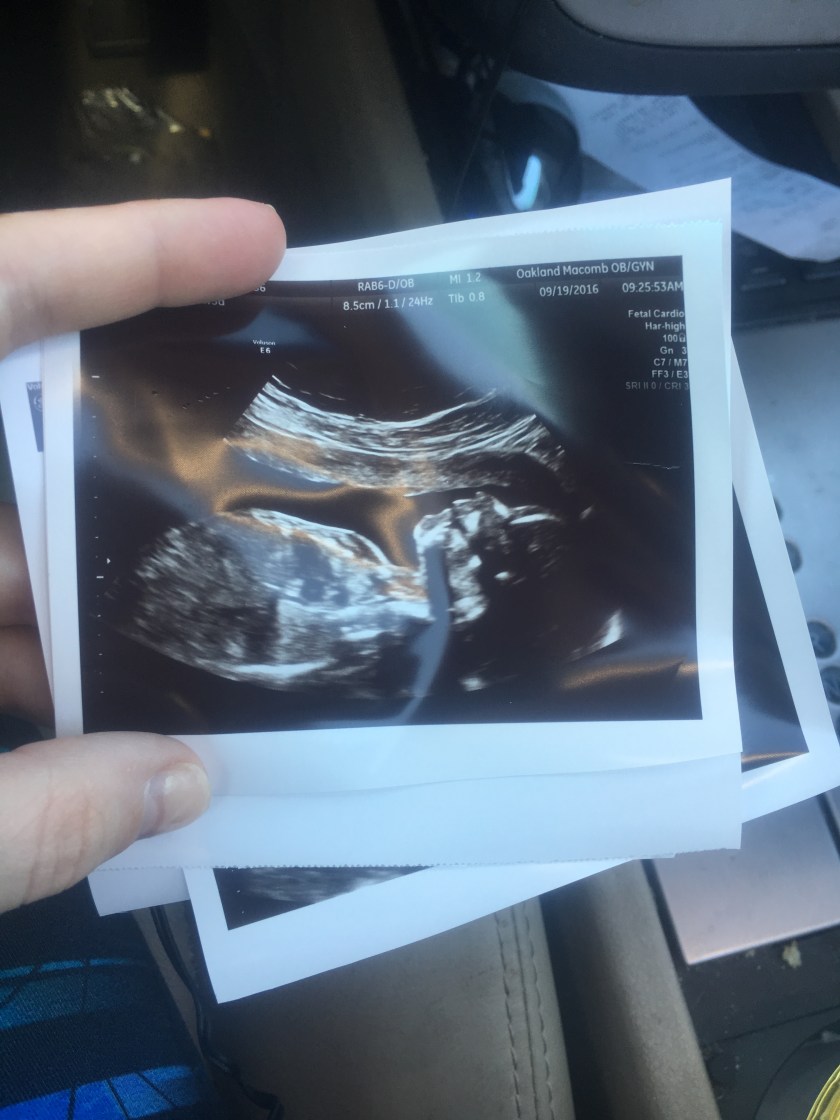

*You were about ready to come out right about here*